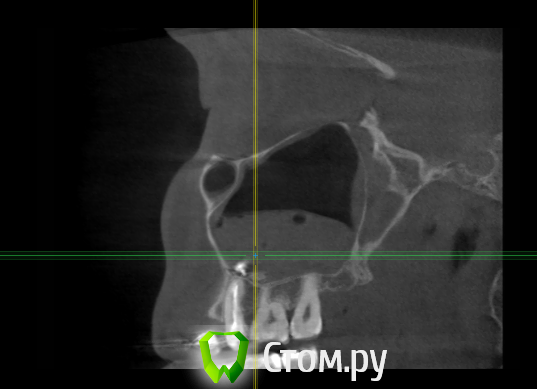

enka Опубликовано 17 апреля, 2014 Поделиться Опубликовано 17 апреля, 2014 Уважаемые доктора, была проблема внчс, теперь после контрольного ОПТГ нашлись еще проблемки! Поясните пожалуйста, что с ними делать? На данный момент ничего не беспокоит (выделений из носа нет, зубы не болят). Спасибо! Ссылка на комментарий

Bier Опубликовано 17 апреля, 2014 Поделиться Опубликовано 17 апреля, 2014 материал в пазухе, надо убирать. Качество пломбировки зубов по этим срезам не понять. Ссылка на комментарий